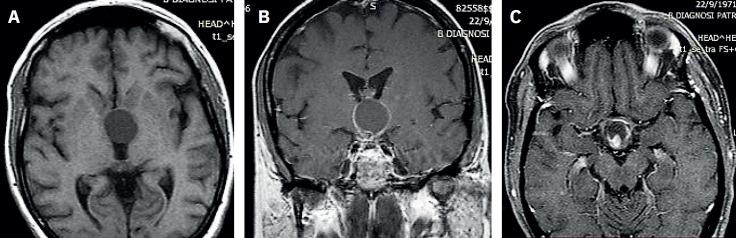

During the work up, the patient complained about bitemporal hemianopsia. Thus, she underwent a pituitary Magnetic Resonance Imaging, which revealed a mixed mass originating from the pituitary stalk and compressing the optic chiasm. The mass was surgically excised, and the histology confirmed the diagnosis of adamantinomatous craniopharyngioma. The patient remained afebrile post-surgery. We hypothesize that the craniopharyngioma caused an abnormality of thermoregulatory mechanisms due to infiltration of the hypothalamus.

在检查过程中,患者主诉双侧颞侧偏盲。因此,她接受了垂体磁共振成像检查,结果显示有一个混合性肿块起源于垂体柄并压迫视交叉。该肿块通过手术切除,组织学检查确诊为造釉细胞瘤型颅咽管瘤。患者术后不再发热。我们推测颅咽管瘤由于下丘脑浸润导致体温调节机制异常。